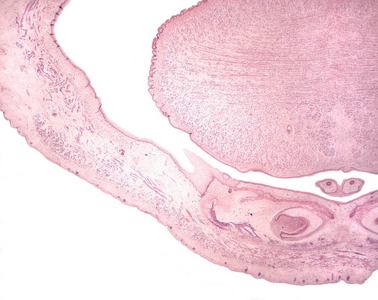

Präparat 45: Zahnanlage, H.-E.

Zahnleiste

erstes Stadium der Zahnanlage in Form von bogenförmigen Absenkungen des Epithels der Mundbucht im Bereich des späteren Ober- und Unterkiefers. An ihrem Ende entwickelt sich die Zahnknospe, aus der das Schmelzorgan hervorgeht.

Zahnsäckchen

Verdichtung des Mesenchyms, das die Zahnanlage umgibt. Aus ihm entwickeln sich die Bestandteile des Zahnhalteapparates.

Es handelt sich um einen Schnitt durch die herausgelöste Maxillar- und Mandibularregion eines menschlichen Embryos. Das Präparat hat also präparationsbedingte künstliche Schnittflächen und zwei natürliche, von Epithelien überzogene Oberflächen: die Haut auf der Außenseite und die Schleimhaut im Innern der Mundhöhle. Die Wangenhaut ist beim Embryo noch nicht so dick und deutlich verhornt wie beim Erwachsenen, läßt sich aber anhand der zahlreichen vom Epithel in die Tiefe eingestülpten Haarfollikel identifizieren. Die stark gebuchtete Mundhöhle (in der u.U. auch die Zunge angeschnitten ist) trägt ein typisches mehrschichtiges unverhorntes Plattenepithel. Schon in der Übersicht erkennt man, daß von diesem Epithel ausgehend im Ober- und im Unterkieferbereich schlauchartige, manchmal gewundene Gebilde (die Zahnleisten) sich in die Tiefe senken, die in epithelialen Verdichtungen, den Zahnknospen der Zahnanlagen enden. Im hier gezeigten Entwicklungsstadium hat sich die Zahnknospe bereits zur Zahnglocke, dem Schmelzorgan, differenziert. Im Inneren der Glocke liegt die Zahnpapille aus verdichtetem Mesenchym. Außen um die Zahnglocke verdichtet sich das Mesenchym zum Zahnsäckchen.